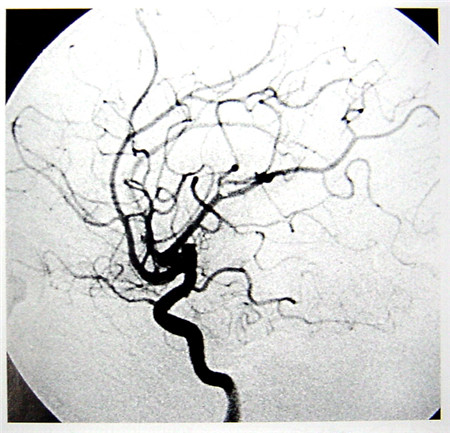

數字減影血管造影(DSA)簡介

數字減影血管造影技術(Digital Subtraction Angiography,DSA)是一種新的X線成像系統,是常規血管造影術和電子計算機圖像處理技術相結合的產物。DSA的成像基本原理是將受檢部位沒有注入造影劑和注入造影劑后的血管造影X線熒光圖像,分別經影像增強器增益后,再用高分辨率的電視攝像管掃描,將圖像分割成許多的小方格,做成矩陣化,形成由小方格中的像素所組成的視頻圖像,經對數增幅和模/數轉換為不同數值的數字,形成數字圖像并分別存儲起來,然后輸入電子計算機處理并將兩幅圖像的數字信息相減,獲得的不同數值的差值信號,再經對比度增強和數/模轉換成普通的模擬信號,獲得了去除骨骼、肌肉和其它軟組織,只留下單純血管影像的減影圖像,通過顯示器顯示出來。通過DSA處理的圖像,使血管的影像更為清晰,在進行介入手術時更為安全。

數字減影血管造影DSA腦血管圖像顯示                                                      核磁共振MRI掃描腦組織圖像